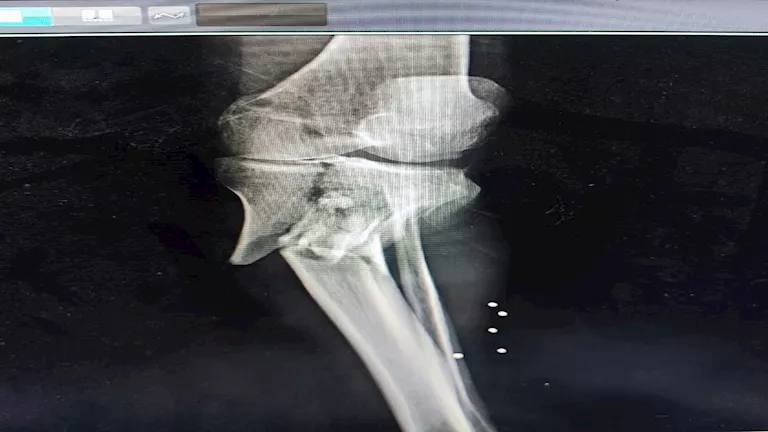

أعلنت مديرية الصحة بالمنيا، اليوم الإثنين، عن نجاح مستشفى صدر المنيا في إجراء عملية جراحية دقيقة لأول مرة لتثبيت كسر مفتوح ومفتت من الدرجة السادسة بالركبة لمريض يبلغ من العمر 58 عامًا.

المديرية، فإن العملية أجريت في تمام الواحدة صباحًا، وتكللت بالنجاح بفضل جهود ومهارة الفريق الطبي المتكامل واستخدم الفريق الطبي تقنية إليزاروف المتقدمة، بالإضافة إلى المسامير، لتثبيت الكسر المعقد، مما يمثل خطوة مهمة نحو تعافي المريض.